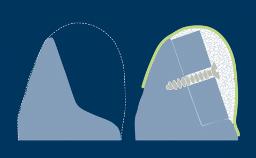

Once a thorough treatment plan is established, different design configurations may be possible for implant-supported prostheses. Each prosthesis design has its advantages and disadvantages.

The prosthesis design must be based on the clinical condition to ensure that the appropriate number of implants are placed in the correct prosthetic positions using implants with appropriate dimensions.